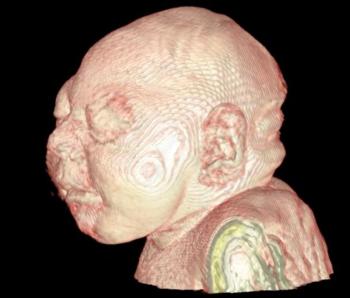

In a third study, ultrasound and fetal MRI were performed on pregnant patients with Zika virus infection at different gestational ages. Once the babies were born, they underwent ultrasound, CT and MRI. The researchers then created 3-D virtual and physical models of the skulls. More than half the babies had microcephaly, brain calcifications and loss of brain tissue volume, along with other structural changes.

"The emergence of Zika virus in the Americas has coincided with increased reports of babies born with microcephaly," said study author Heron Werner Jr., M.D., Ph.D., from the Department of Radiology at Clínica de Diagnóstico por Imagem. "An early diagnosis may help in treating these babies after birth. Moreover, the knowledge of abnormalities present in the central nervous system may give hints about the pathophysiology of the disease."